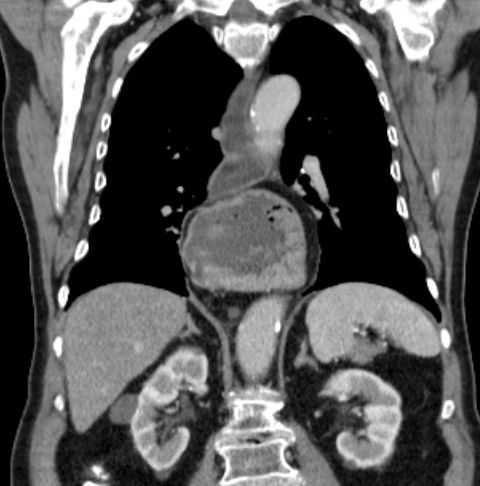

Hiatus - Hernie 83-jähriger Patient, der seit 2 Wochen Schluckbeschwerden mit unmittelbarem Erbrechen nach Nahrungsaufnahme hat. Das CT zeigt eine breite Zwerchfellhernie mit Teilen des Magens.

Die hintere Wand des intrathorakalen Magens ist verdickt: Adenokarzinom.

Der Ösophagus ist dilatiert und distal wandverdickt.